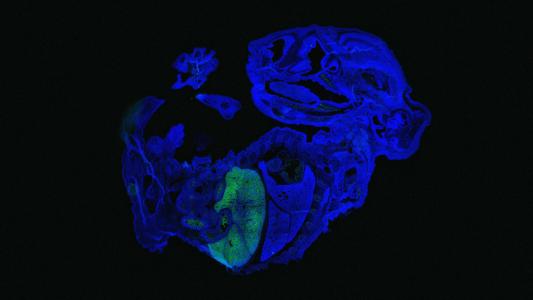

Stem cell research breakthrough opens path to growing human organs in animals